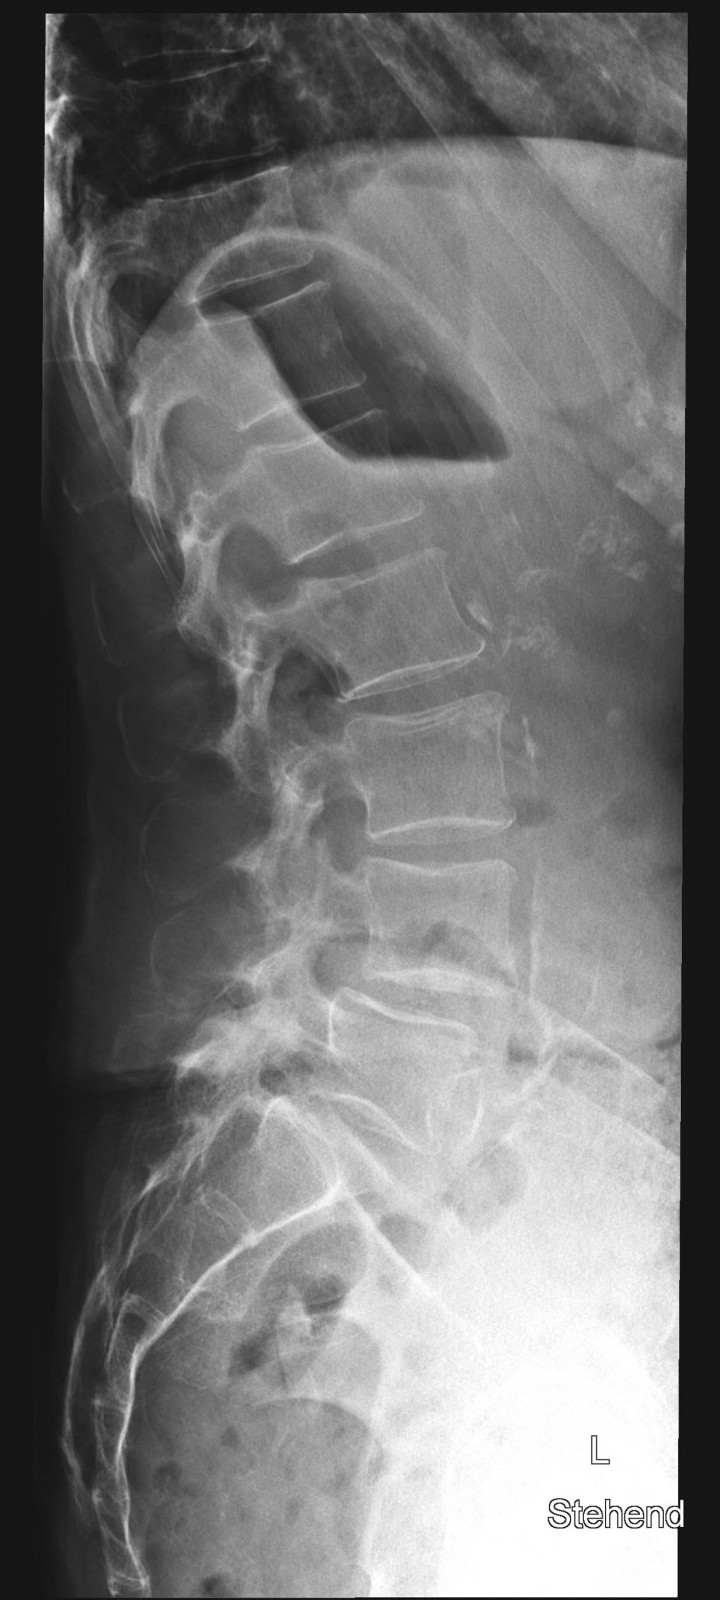

Röntgenfall des Monats März 2017 mit Auflösung

80 jährige Patientin mit chronischen linksbetonten Schmerzen lumbal am Übergang zum Becken

WS seitlich

Bild vergrössern